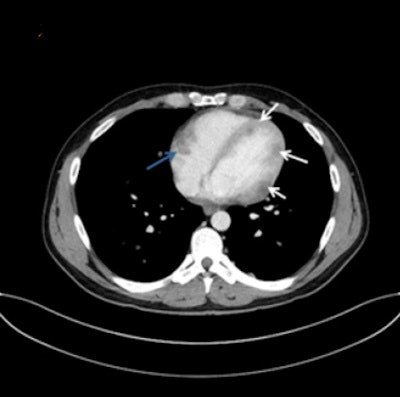

Metastases along the endocardium with polypoid growth into cardiac cavities were classified as endocardial metastases, and these patients were assigned to group 1. Metastases located in the myocardium with infiltrative growth were classified as myocardial metastases, and patients were assigned to group 2. Patients with metastases of the pericardium were assigned to group 3.

Fourteen out of 25 patients presented with singular cardiac mass (56%), whereas 10 patients (40%) presented with multifocal metastases, and one patient with disseminated metastases. Twelve patients presented with endocardial (48%), eight with myocardial, and two with pericardial metastases. The most frequent site involved in endocardial metastases was the right atrium (67%), followed by the right ventricle (33%).